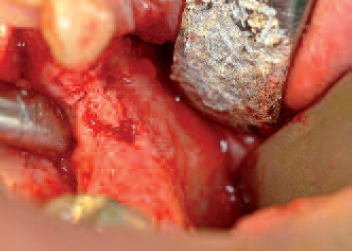

Presentation of bone defect (above all horizontally) after implant drilling in region 12

Inserted guide elements after removal of the osteosynthesis materials four months post operationem

Autologous bone material positioned on top of the defect; collagen membrane palatally fixed with suture